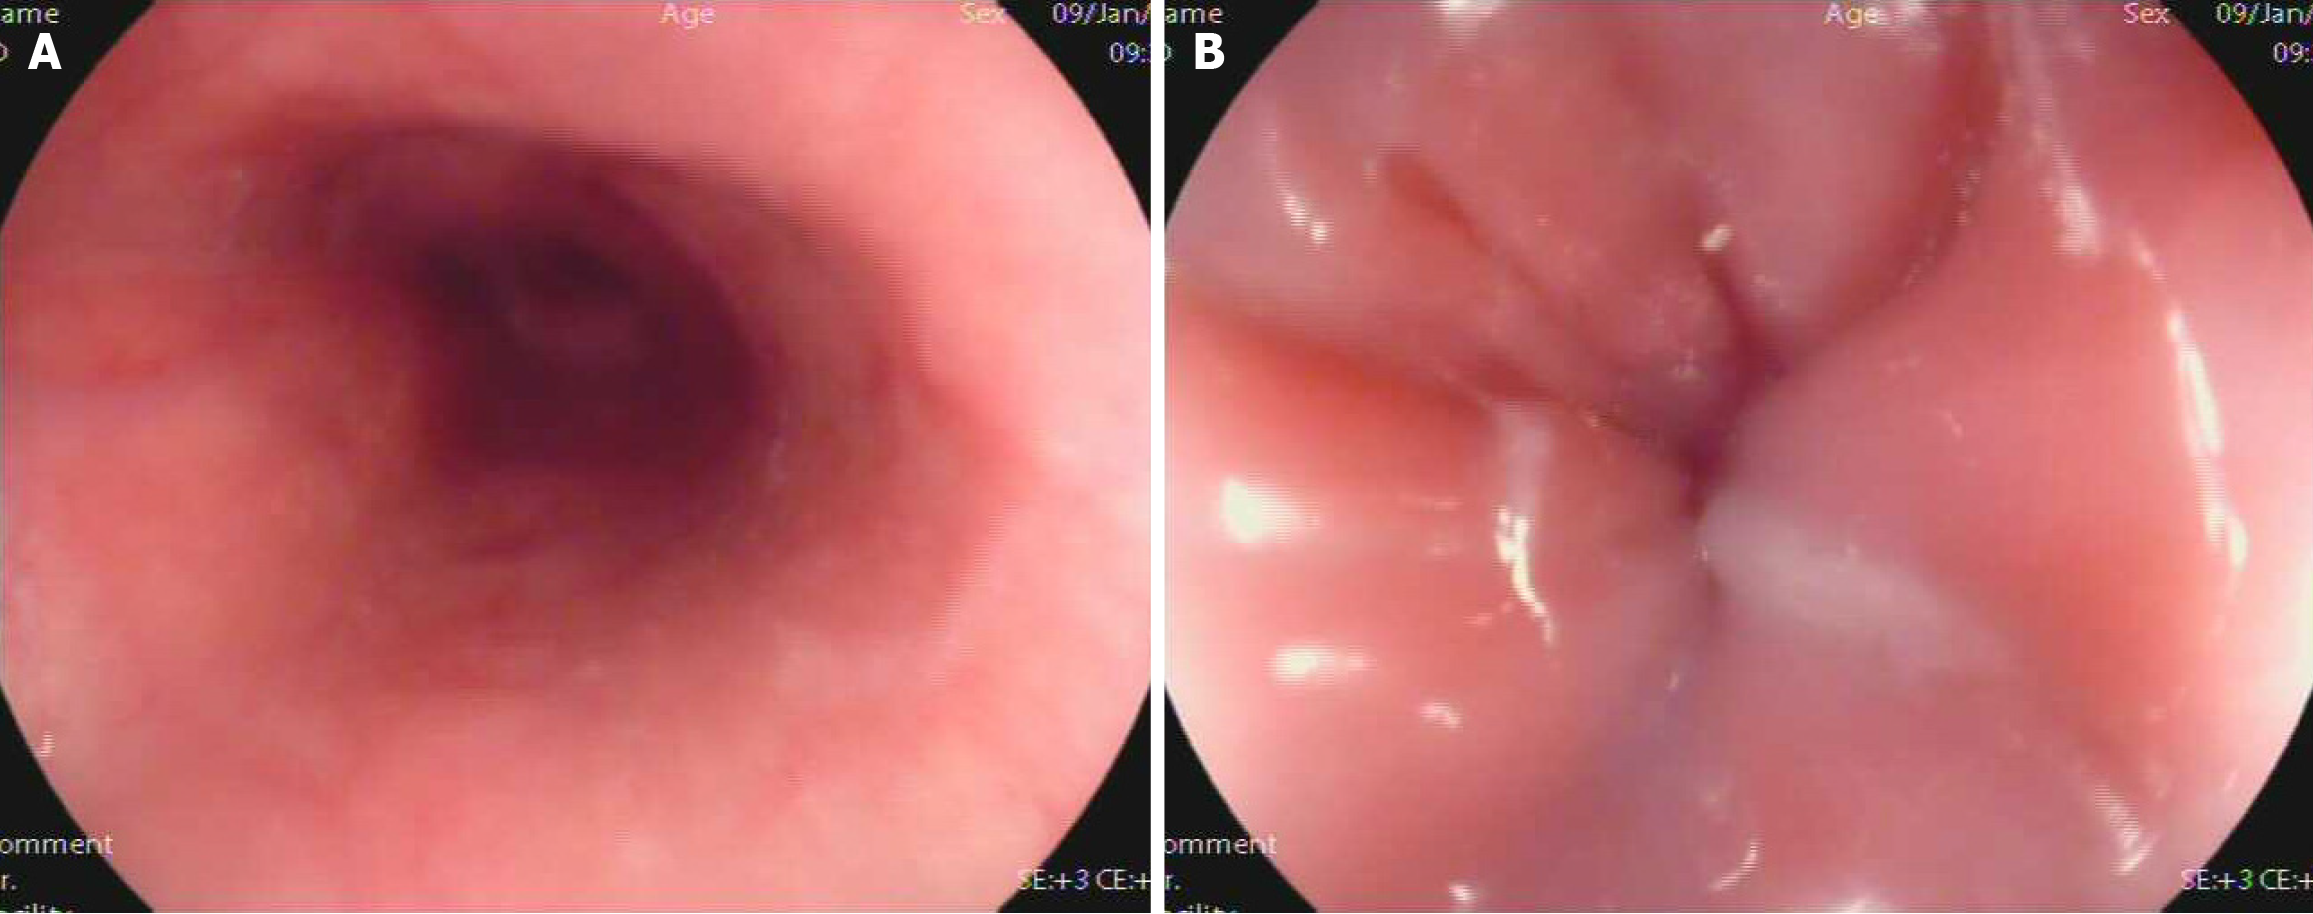

Figure 2 Gastroscopy view of the patient.

A and B: In January 2017, gastroscopy revealed a smooth esophagus mucosa and a severe cardiac stenosis, the gastroscope was unable to pass through.